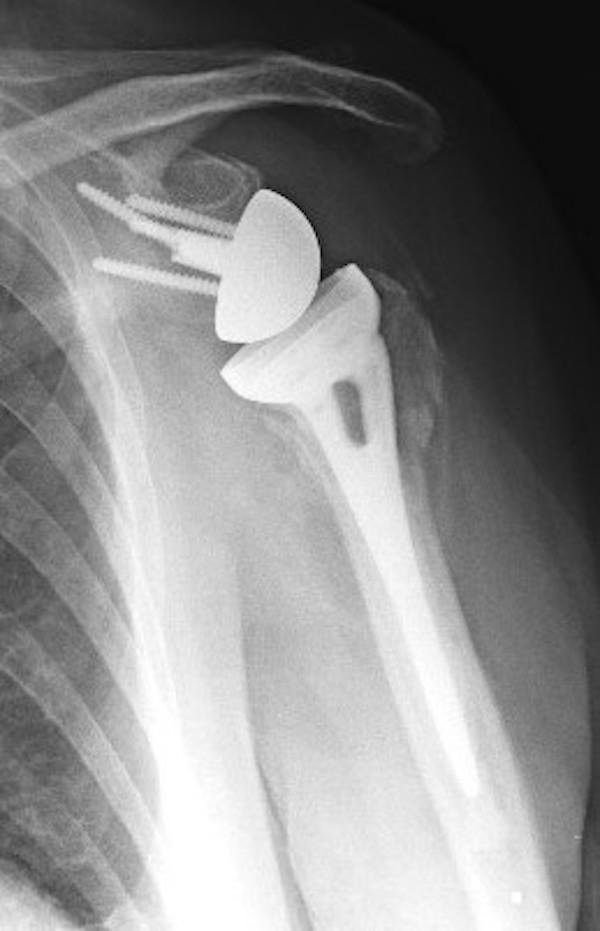

The procedure is called a “reverse” because it changes the position of the joint components: the ball-shaped implant is placed where the shoulder socket (glenoid) once was, and the socket is positioned where the humeral head used to be. This reversed design shifts the mechanics of the shoulder, allowing the deltoid muscle to take over much of the work normally done by the rotator cuff. By relying on the deltoid instead of the torn rotator cuff, reverse shoulder replacement may help restore shoulder movement, improve stability, and significantly reduce pain in patients who are no longer candidates for conventional anatomical replacement.

The glenosphere replaces the ball of the shoulder joint, but unlike a traditional shoulder replacement, it is fixed to the shoulder blade rather than the upper arm. It attaches securely to a metal baseplate that is anchored to the glenoid using screws. The rounded metal design creates the new “ball” of the joint and shifts the centre of rotation, allowing the deltoid muscle to raise the arm even when the rotator cuff is not functioning. Different glenosphere sizes can be selected to match the patient’s anatomy and support joint stability and mobility.

The humeral cup replaces the socket part of the joint. It is a smooth, concave liner, often made from durable polyethylene, and is designed to articulate with the metal glenosphere. The cup provides a stable surface for controlled, balanced movement and allows the deltoid muscle to power the joint. Variations in cup depth, shape, and angulation enable the surgeon to fine-tune joint tension and movement, helping to maintain stability during everyday activities such as lifting and reaching.

The humeral stem sits inside the upper arm bone and forms the foundation for the humeral cup. It is typically made from strong, biocompatible metal, and may be inserted with or without cement depending on bone quality. The stem supports the prosthesis, distributes load through the arm bone, and helps maintain alignment during shoulder movement. Different stem lengths and designs allow the implant to be matched to the patient’s anatomy, contributing to the long-term stability of the overall construct.

When the components of a reverse shoulder replacement are assembled, they work together to shift the centre of rotation, giving the deltoid muscle improved leverage to lift and control the arm. This design enhances stability when the rotator cuff is no longer functioning and allows the joint to move through a more efficient biomechanical pathway. As a result, many people can regain practical movement for everyday tasks such as reaching, lifting the arm, and dressing.

Dr Hockings begins by removing the damaged joint surfaces and preparing both the glenoid and humerus with precision. The prosthetic components are then inserted in a reversed configuration, where the ball is placed on the shoulder blade and the socket is positioned on the upper arm bone. This design allows the deltoid muscle to take over the work of a deficient rotator cuff.